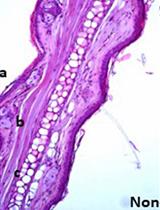

Hepatitis B virus (HBV) can cause both acute and chronic disease in human liver with potentially high risk of cirrhosis and liver cancer. The host range of non-human primates susceptible to this virus is limited. Therefore, experimental studies with human hepatocyte-chimeric mice provide an invaluable source of information regarding the biology and pathogenesis of HBV. This section describes the protocol for infection of the human hepatocyte-chimeric mice with HBV. In addition, it has recently been shown that HBV replication can be suppressed by exogenous expression of viral epsilon RNA (εRNA; Sato et al., 2015), which serves as an encapsidation signal (Bartenschlager et al., 1992). Based upon this finding, we also describe the protocol for the liposome-mediated delivery of a plasmid encoding εRNA to liver in these chimeric mice.